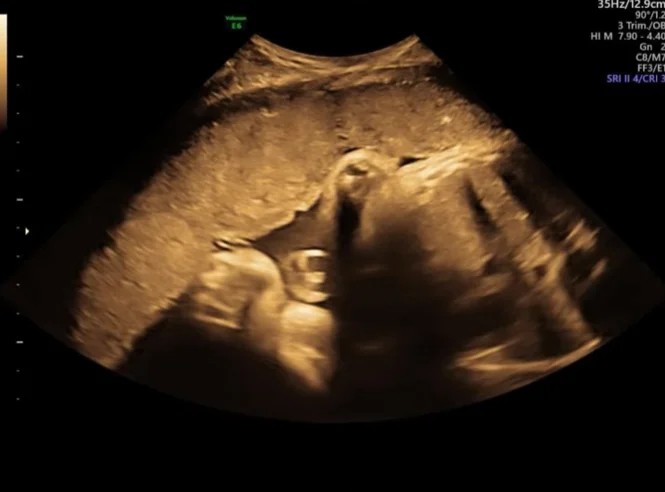

Nhiễm Cytomegalovirus (CMV) bào thai

01/04/2026